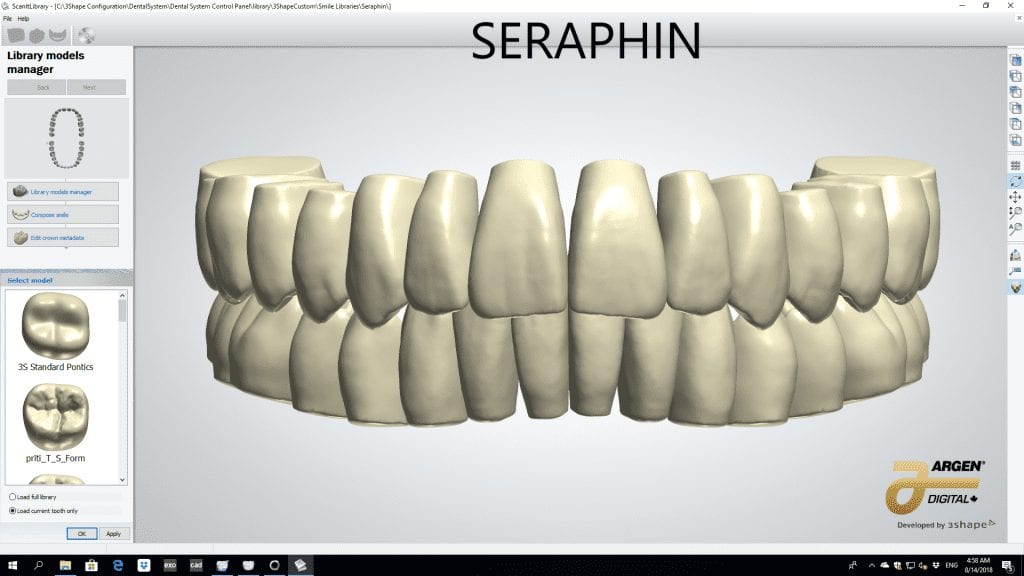

The digital models were then imported into a third party software where a library of tooth morphologies are available for the clinician to choose from.

Once the appropriate library is chosen, the digital wax ups are performed. In the subsequent photos you can see the transparent overlay of the wax-ups to the original position of the existing dentition